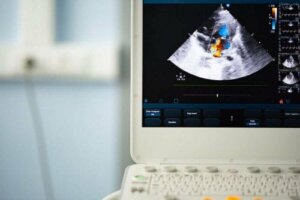

Kontrol sırasında düzensiz kalp çarpıntısını duyabilmek ve ayrıca bir kalp hırıltısı belirtileri için bir stetoskop kullanabilirler. Bundan sonra, biküspit bir aort kapağınız olduğunu doğrulamak için kalbin nasıl çalıştığını değerlendirmeye yardımcı olan bir ekokardiyogram yapacaklardır.